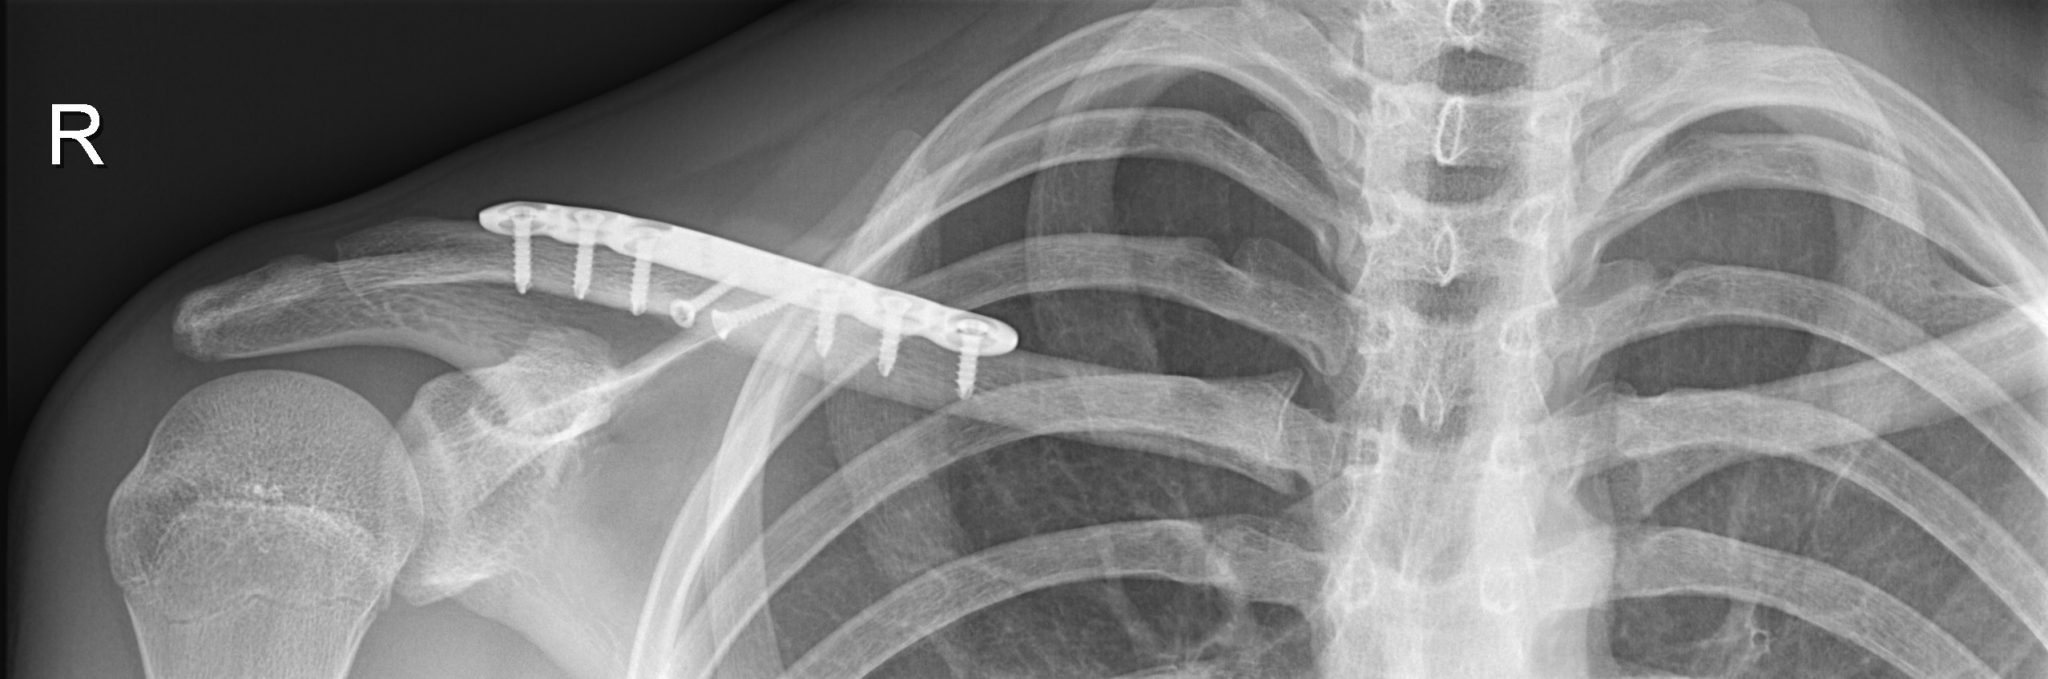

Behandeling hangt af van de aard van de breuk. Niet-verschoven breuken kunnen conservatief worden behandeld met een draagdoek, rust en ontstekingsremmende medicijnen. Bij gecompliceerdere breuken, fors verplaatst of verkort, kan chirurgische interventie nodig zijn, waarbij botfragmenten worden gezet en gefixeerd met platen en schroeven.